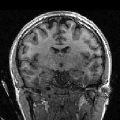

In order to evaluate the impact of such smoothing, classification tests have been conducted based on images reconstructed with both methods. Gray and white matter classification results using the Morphologist 2012 pipeline of -MRI toolbox of Brainvisa software444http://brainvisa.info at and are compared to those obtained without acceleration (i.e. at ), considered as the ground truth. Displayed results in Fig. 2 show that classification errors occur due to reconstruction artifacts for mSENSE, especially at . Results show that the gray matter is better classified using our 3D-UWR-SENSE algorithm especially next to the artifact into the red circle (Fig. 2 []), which lies at the frontier between the white and gray matters. Moreover, reconstruction noise with mSENSE in the centre of the white matter (left red circle in Fig 2 []) also causes miss-classification errors far from the gray/while matter frontier. However, at and classification performance is rather similar for both methods, which confirms the ability of the proposed method to attenuate reconstruction artifacts while keeping classification results unbiased.